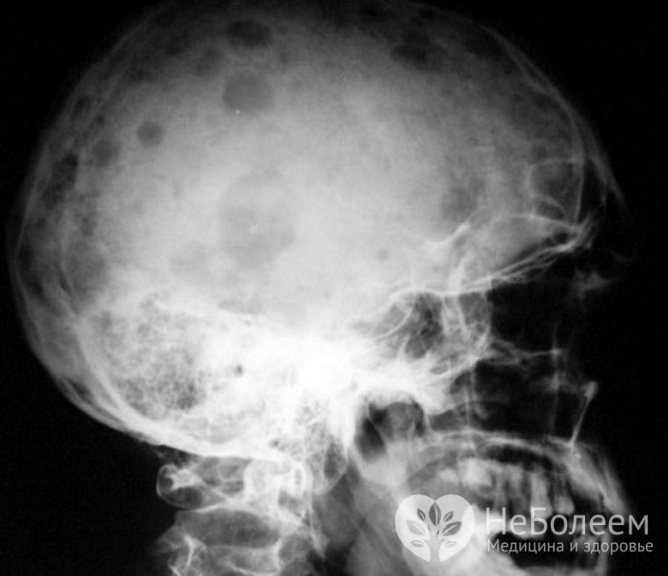

Миеломная болезнь – рентген

Важнейших этап исследования при миеломной болезни – рентген. Диагноз множественная миелома диагностика с помощью рентгенографии может полностью подтвердить или оставить под вопросом. Опухолевые очаги при рентгене видны отчетливо, а кроме того – врач получает возможность оценить степень поражения и деформации костных тканей. Диффузные поражения на рентгене выявить сложнее, поэтому врачу могут потребоваться дополнительные методы.